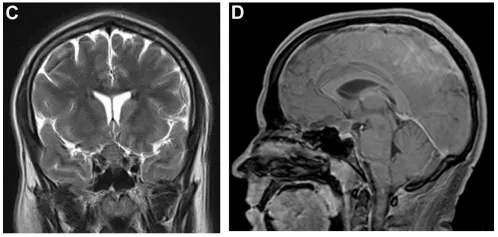

然而,一年零一个月后,患者再次出现剧烈头痛,伴双眼发黑持续约半小时。增强MRI检查发现肿瘤复发,与垂体腺分界不清,再次沿蝶骨平台和斜坡颅侧生长。新出现的强化信号提示肿瘤性质可能发生改变(图2)。此次眼科检查发现右眼中心暗点及红色色觉异常。

图2.(A、B)矢状位及轴位T1加权增强MRI显示鞍区及鞍上占位复发,与垂体腺分界不清,病灶再次沿蝶骨平台及斜坡颅侧延伸。(C)梯度回波序列显示病灶呈显著磁敏感效应,并新出现强化灶。